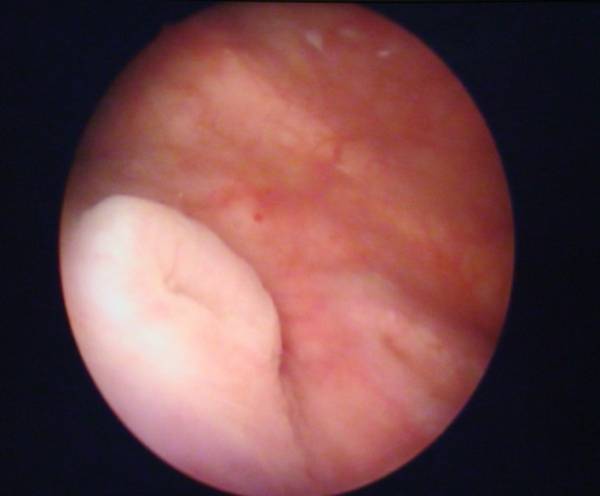

- цистоскопия — в уретру вводится цистоскоп, оснащенный видеокамерой, что позволяет детально осмотреть всю внутреннюю поверхность мочевого пузыря. Во многих случаях такая диагностическая операция проводится под анестезией;

Известны многочисленные случаи, когда лейкоплакия ошибочно диагностировалась как цистит, что объясняется близкой симптоматикой. Поскольку методы лечения этих патологий существенно различаются, после начала терапии состояние пациента постепенно ухудшается. Такой проблемы можно избежать, если проводить обследование, включающее в себя цистоскопию, сразу же после появления первых симптомов болезни. При визуальном осмотре внутренней стенки мочевого пузыря у больных лейкоплакией заметны характерные внешние изменения пораженных участков, тогда как при цистите подобных признаков нет.

- плоскоклеточная метаплазия становится хорошо заметной при визуальном осмотре внутренней стенки мочевого пузыря (в процессе цистоскопии). Площадь пораженных областей увеличивается;